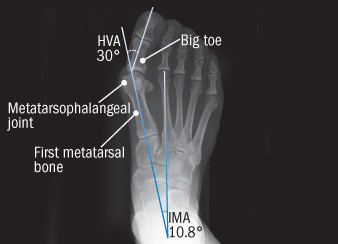

Anatomy of a bunion

Photo courtesy Dr. James P. Ioli A bunion is most likely to develop when susceptible feet are repeatedly squeezed into narrow, pointed-toe footwear. The big toe pushes against the other toes, sometimes diving over or under them. As a result, the base of the big toe — the metatarsophalangeal (MTP) joint — juts or angles out from the foot. To judge how severe a bunion is, clinicians take an x-ray and measure angles between certain bones in the foot, in particular, the hallux valgus angle (HVA) — the angle between the first metatarsal and the big toe — and the angle formed by the first and second metatarsals, called the intermetatarsal angle (IMA). The upper limit of normal for the HVA is 15 degrees; for the IMA, 9 degrees. |